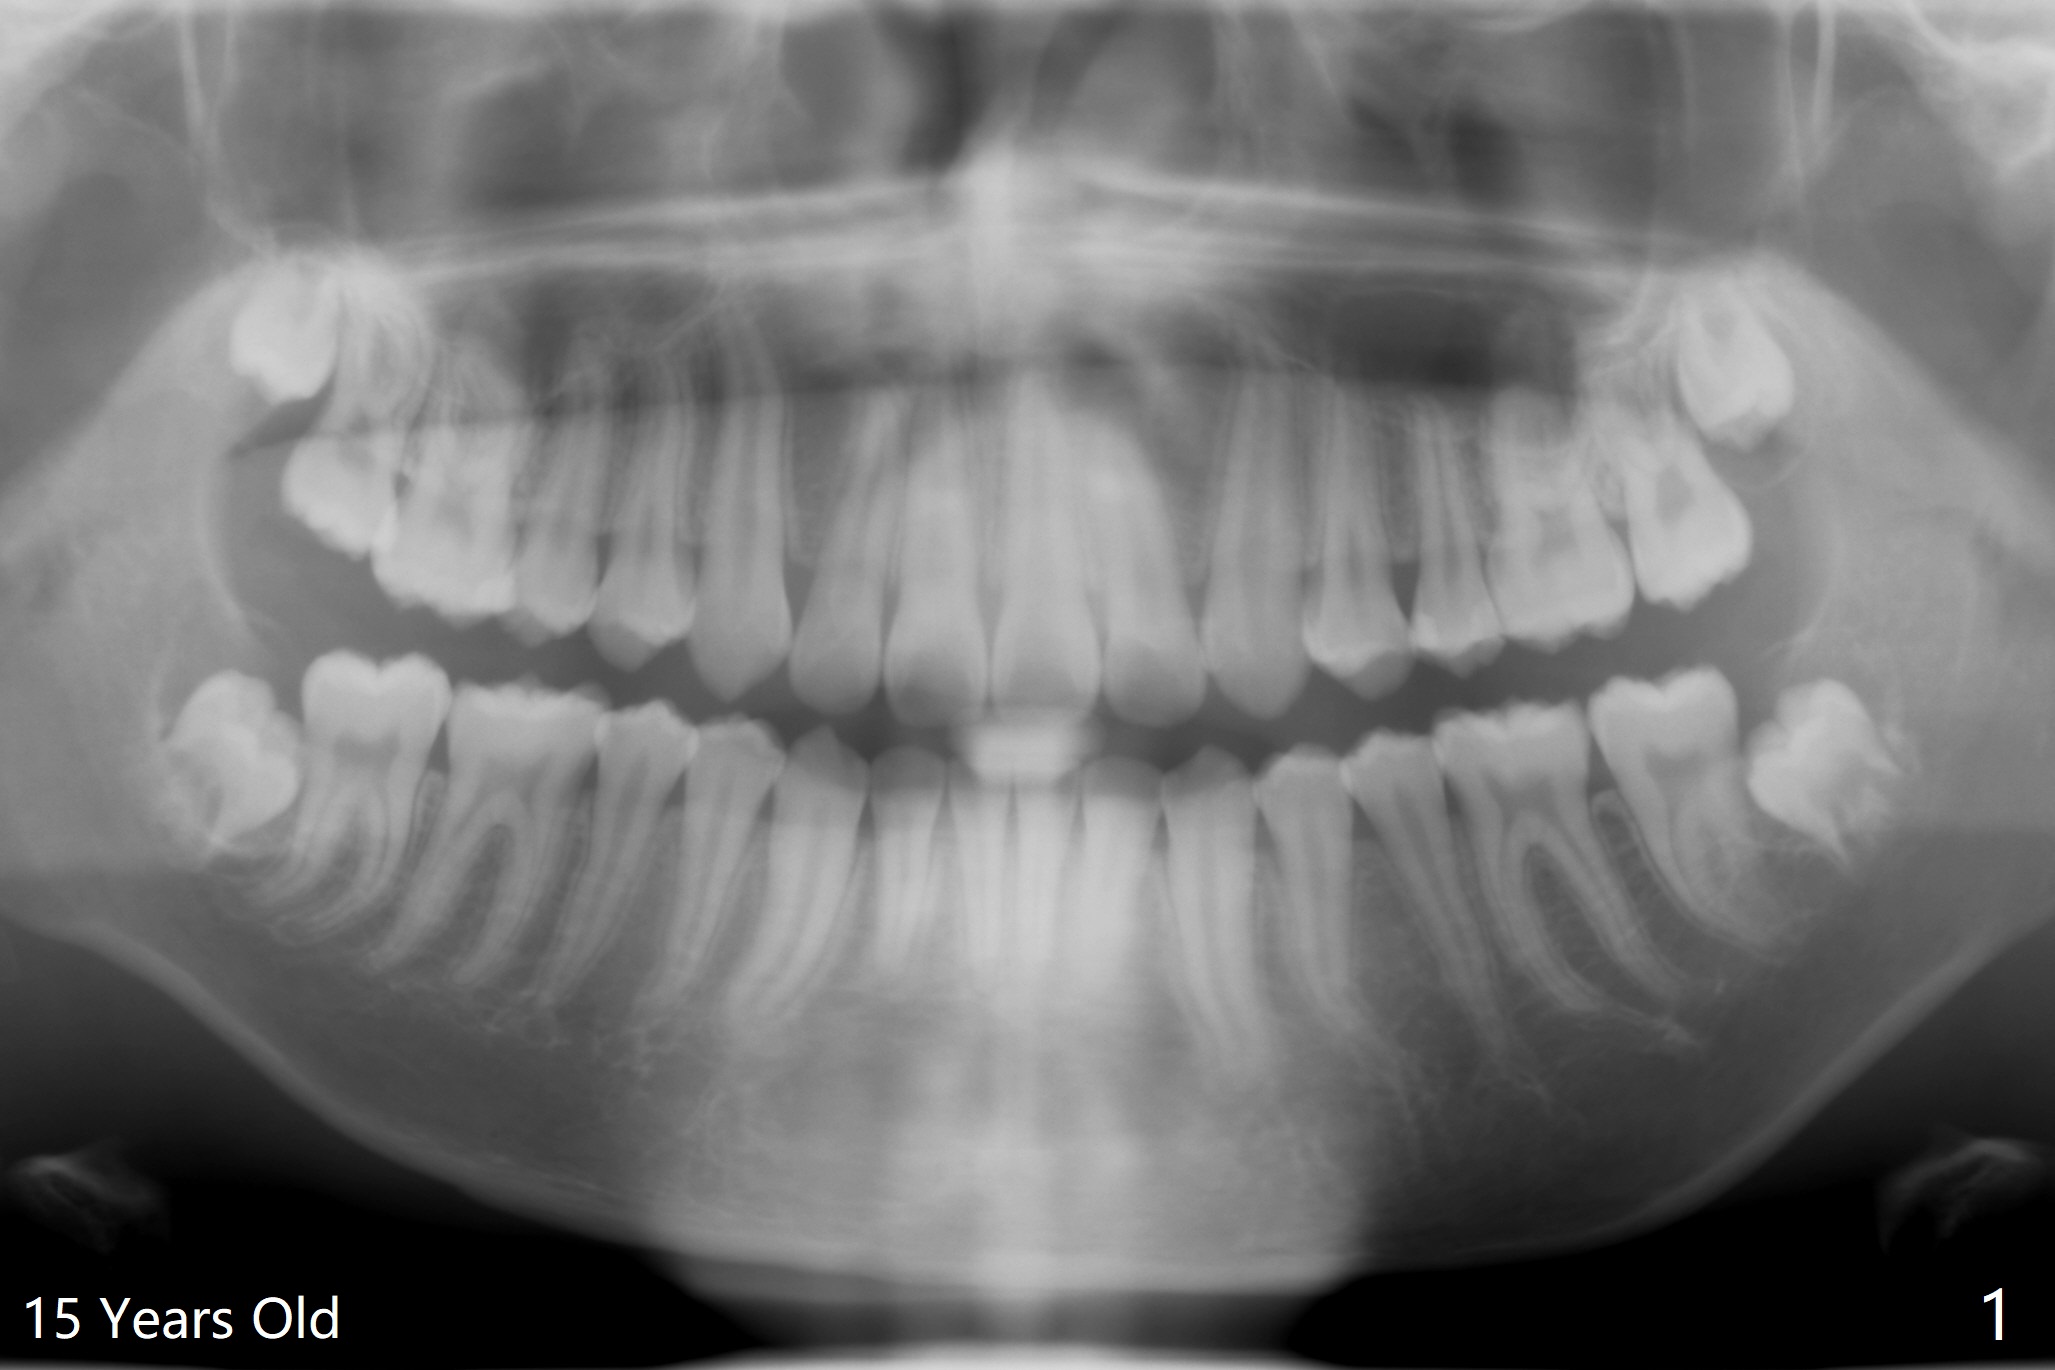

A 19-year-old man returns for #1,16,17 and 32 extraction (Fig.1,2). Because of horizontal impaction of #32 and no bone #31 distal post extraction (Fig.3 *), 3D bond (.5 cc) will be placed in the mesial socket of #32 (Fig.4 red), while Osteogen plug (1/2 (O)) in the distal one. Since there is no bony defect between #17 and 18 after extraction (Fig.5 *), a piece of Osteogen plug (cut half apical) will be inserted in #17 socket, whereas 2 small pieces of Osteogen plug placed in the apical portions (triangle and spindle shaped). Take posterior panoramic X-ray postop (bitewing type, CT format, not XV). There appears bone formation in the socket 5 months postop (Fig.10,11).

Since #32 sockets seem large, extending mesiobuccal (Fig.6), Bond Apatite (1 cc) is placed instead (Fig.7 B), covered by 1/3 of Osteogen plug (O) and sutured with 4-0 PGA. Extraction of #17 is also difficult. As 2 sockets are indistinct, a piece of Osteogen plug with split is placed (Fig.8) upside down (Fig.9 vs. Fig.5). There appears bone formation in the socket 5 months postop (Fig.10,11).